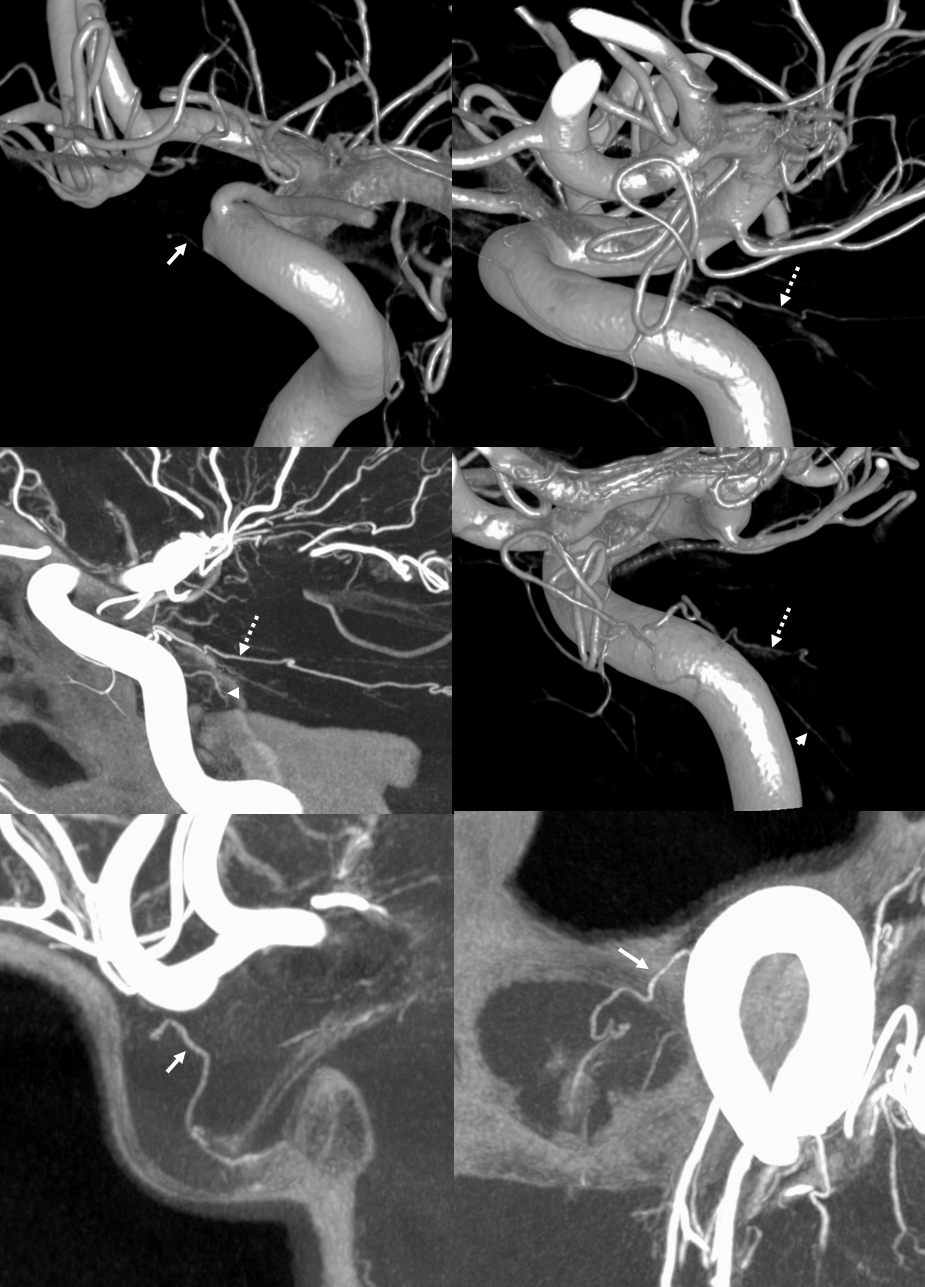

Supply of the Hypophysis and Balance

As always neuroangio is about balance. There may be one or more superior hypophyseal arteries. Usually one is visible by cone beam/flat panel CT. Sometimes more than two. Here there are 3. Nicely shown is supply of the stalk (open arrow). There is also likely contribution to the optic chiasm, which is of course very important. The inferior hypophyseal branches (dashed arrow) from the MHT support the posterior pituitary. The ILT is hypoplastic, with lateral branches of the MHT (white arrowhead) heading towards the meckel cave and the recurrent branch along the tentorial edge (black arrowhead) supplying territory normally done by the ILT

Without labels

Optic Nerve Supply

What supplies the bulk of optic nerve? Central Retinal artery is for the distal portion of nerve and retina. What about the rest — intracranial, intracanalicular, proximal intraconal segments? The answer is not clear (let me know if you do), but i believe the bulk of it comes from the superior hypophyseals. It is probably in balance with the recurrent branch of the central retinal artery. Below is an example of an especially prominent proximal-most superior hypophyseal (arrows) supplying the pituitary stalks and optic nerve in the canalicular and intracranial locations. Note how well one can see the branch in coronal view (bottom left image). In this case there are two large superior hypophyseals — the more distal one (dashed arrows) supplies predominantly the pituitary stalk. The inferior hypophyseal artery is marked by arrowhead. Lower right image is coronal.

Movie is the best way

Here too superior hypophyseal (arrow) supply of the intracranial optic nerve (oval) and possibly chiasm is shown definitively (lower right image is coronal)

No annotations

Pattern of optic apparatus supply and unusual hypophyseal ILT vessel

VR — the anterior-most branch of the superior hypophyseals is usually the largest (arrow). The others are too small to see on a VR image

MIPS. The anterior, proximal-most branch (arrow) tends to supply the optic nerve (white oval), while the more posterior branches (dashed arrows), when present, supply more posterior structures such as chiasm and tract (dashed oval)

More Optic Nerve Supply — its easier to see on MIPS, but with the right windowing, and stereo, VR imaging is also possible. Here, there are 3 superior hypophyseals seen. The anterior-most (arrow) is usually the largest, suppling the optic nerve (dashed arrow) and chiasm (ball arrow). The middle and posterior hypophyseals (arrowheads) supply the stalk.

Stereo of VR image. Same arrows. The stalk is open arrow.

Another patient — also 3 arteries. Cave origin of the anterior-most (arrows) one. The middle one (arrowheads) also supplies the optic nerve. The posterior one (dashed arrows) is for the stalk.

VR images (stereo pair on bottom). The cave origin of the anterior branch is most beautifully seen in the upper right image.